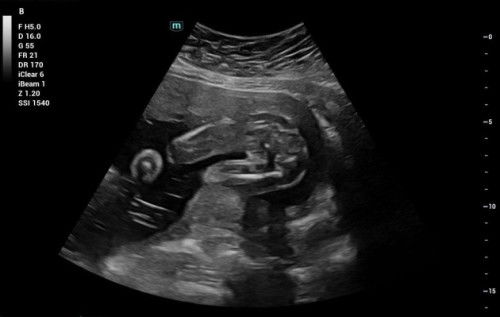

girl kot sbb line kat tgh2 tu jelas sgt.Kalau boy tkde line nmpk pistol

Selalu kalau tak nampak or ade 3 line, selalunya girl. Ini doc yg info huhu

girl..saya pn scan nmpk mcm ni..alhamdulillah sdh melahirkan baby girl

girl...x da pistol..hanya nmpak lurus je..sya punya pun girl😄

nampak mcm girl .. sya pun baby girl 🤗

GIFGegirl, nampak burger lahh 😍😍😍